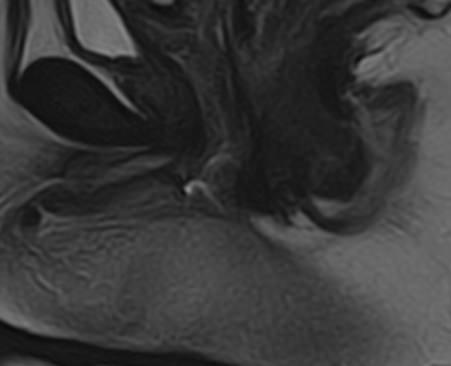

МРТ аноректальной области с контрастным усилением – это специализированное исследование, используемое для детального изучения структур и патологий в области ануса, прямой кишки и окружающих тканей. Контрастное усиление помогает улучшить видимость кровеносных сосудов и определить границы патологических образований.

Преимущества МРТ аноректальной области включают высокую детализацию мягких тканей и отсутствие ионизирующего излучения. Контрастное усиление помогает лучше визуализировать сосуды и патологические изменения.

В целом, МРТ с контрастным усилением является безопасной и информативной процедурой для диагностики различных заболеваний аноректальной области.